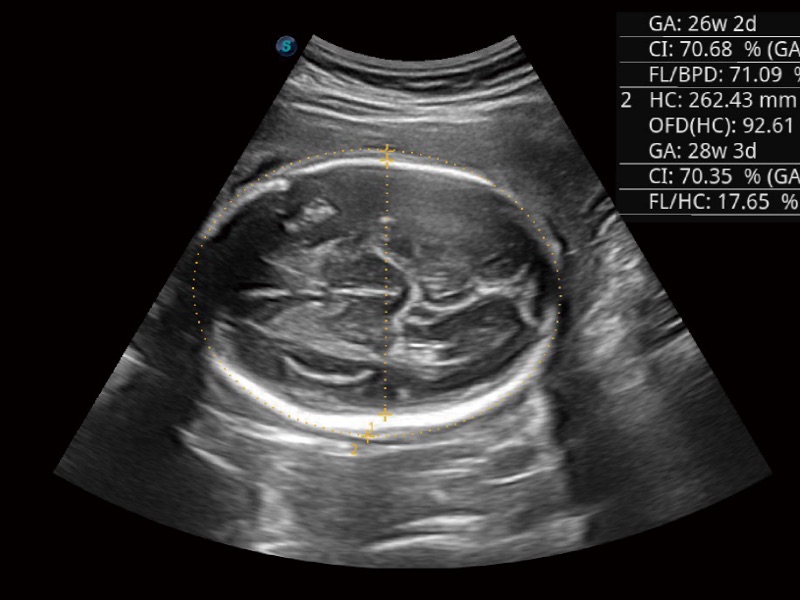

• 妇产科应用

• 光影成像

三维光影成像技术采用新型的渲染方式,增强边缘信息,使得轮显示清晰完整,为临床提供丰富、直观的三维结构,提供临床诊断准确性。

临床图